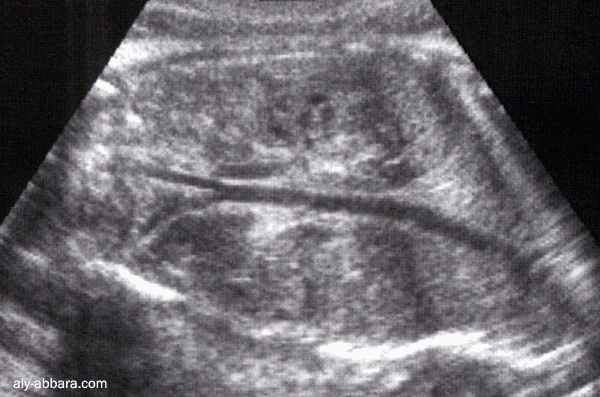

Aorte fœtale

vue par une coupe passant par le tronc fœtale